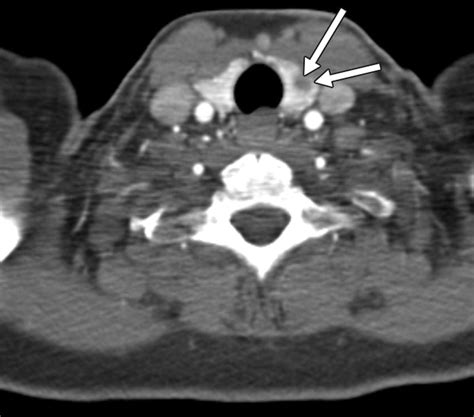

• Computed Tomography (CT) Scan: CT scans can provide additional information about the nodule’s location and any potential invasion into surrounding tissues.